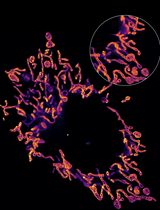

- Supplement objective lens (1.46 NA 100x oil immersion objective) with immersion oil and mount sample on microscope stage (Figure 1 and see

https://applications.zeiss.com/C125792900358A3F/0/8DF1FE51A0C52599C1257C1D0073F96D/$FILE/EN_41_011_061_ELYRA.pdf for microscope setup). - Locate sample using eyepiece and set up a 2 dimensional (2D), 2 color dSTORM (Endesfelder and Heilemann, 2015) experiment using the 488 nm and 641 nm excitation laser lines in separate tracks with the appropriate filters (a possible setup for this pair of dyes would be BP420-480/BP495-560/LP650). See Figure 2 (left) for parameter settings in Zen software.

- Locate a cell and position it in the center of the field of view (FOV) then refocus, ensuring that the entire cell membrane is clearly in focus (Figure 2 [right] for example image).

Figure 1. STORM imaging set-up. 1. Microscope: Axio Observer, Z1 (inverse stand); Incubator XL dark; Motorized Piezo XY scanning stage; Z-Piezo stage insert; Port for LSM attachment; two camera ports. 2. Objectives: Plan-APOCHROMAT 100x/1.46 Oil (DIC). 3. ELYRA Illumination and Detection: Fiber coupled solid state and diode pumped solid state lasers; 405 nm diode (50 mW); 488 nm OPSL (100 mW); 561 nm OPSL (100 mW); 642 nm diode (150 mW); Andor iXon 897 EM-CCD camera. 4. Software: ZEN (black edition), PALM module.

Figure 2. Zen settings for acquisition parameters (left) and Example image (right). Left: 1. Excitation lasers and power; 2. Tracks; 3. Emission filter; 4. TIRF setting and angle; 5. Number of frames; 6. Exposure time; 7. EM gain. 8. Frames per cycle.